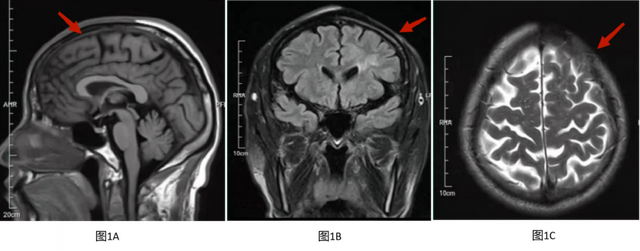

图2 A T1WI轴位左额顶叶皮层下白质低信号;图2B T2WI轴位左额顶叶皮层下白质高信号;图2C T2WI压水相左额顶叶皮层下白质高信号;图2D DWI左额顶叶皮层下白质稍高信号;图2E ADC相左额顶叶皮层下白质稍高信号;图2F T1WI增强无强化